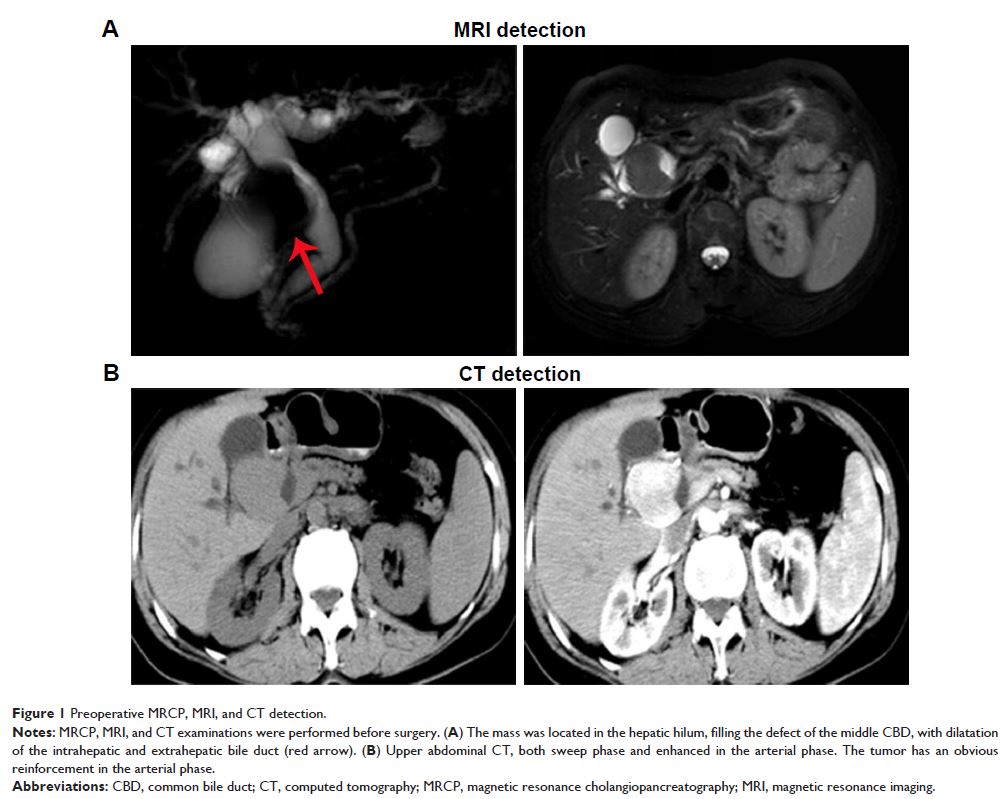

Case Report

- 作者:Zhong Liu, Deng-Yong Zhang, Zheng Lu, Pei Zhang, Wan-Liang Sun, Xiang Ma, Hua Wu, Bin-Quan Wu, Shuo Zhou

- 期刊:OncoTargets and Therapy